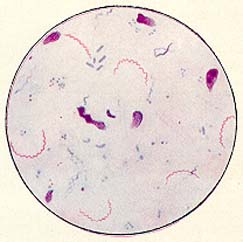

Лептоспиры: фотографии удивительных микроорганизмов